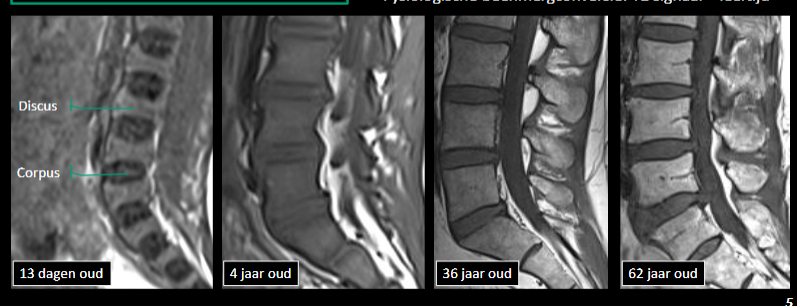

Wat kunnen we kenmerkend op MR herkennen?

Beenmerg, disci, uittedende wortels, ruggemerg, meningen, ligamenten

kenmerken T1 venster

Hypointens: vocht , hyperintens: vet, beenmerg

kenmerken T2 venster

hyperintens: vocht, vet, disci (nucleus pulposus), CSV